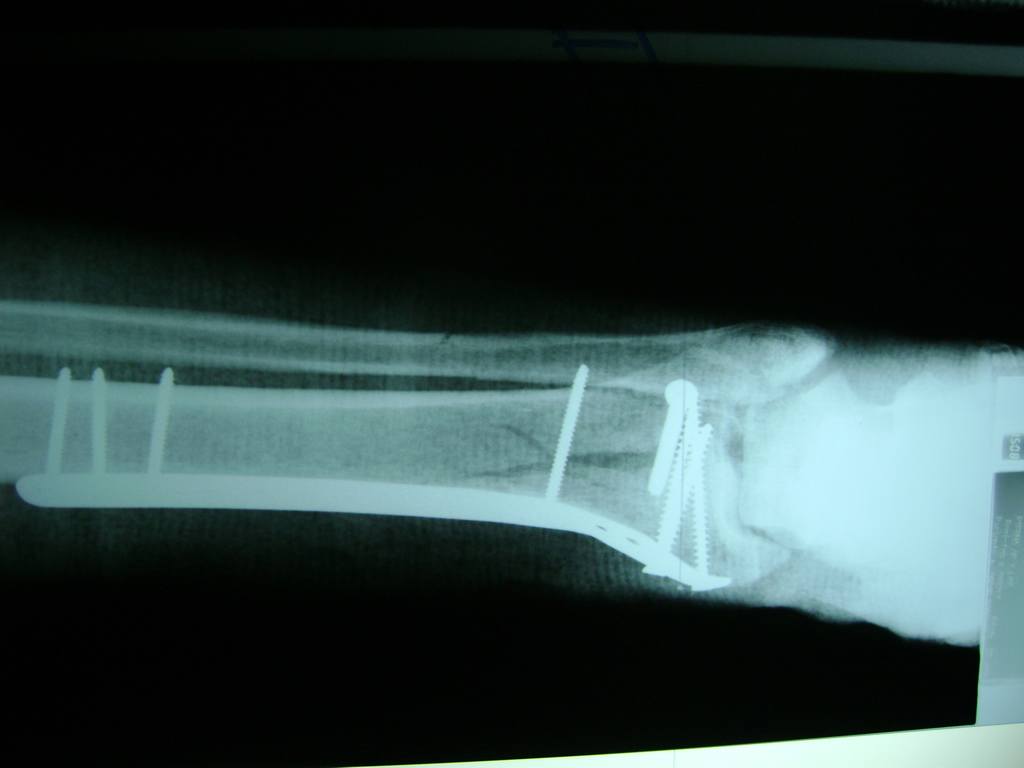

Cirugías de Tobillos

Aunque cada uno de estos huesos puede fracturarse por separado, normalmente la rotura es una lesión que se produce de forma conjunta

La mayor parte de las roturas implican a la parte proximal del hueso (parte del hueso próximo a la rodilla) o a la parte distal (parte del hueso cerca del tobillo).

Debido a la fina cobertura de piel que recubre la tibia y el peroné, las fracturas generalmente son abiertas, es decir, el hueso roto rasga la piel, atravesándola. Las fracturas de tibia y peroné generalmente se producen por un fuerte impacto o torsión.